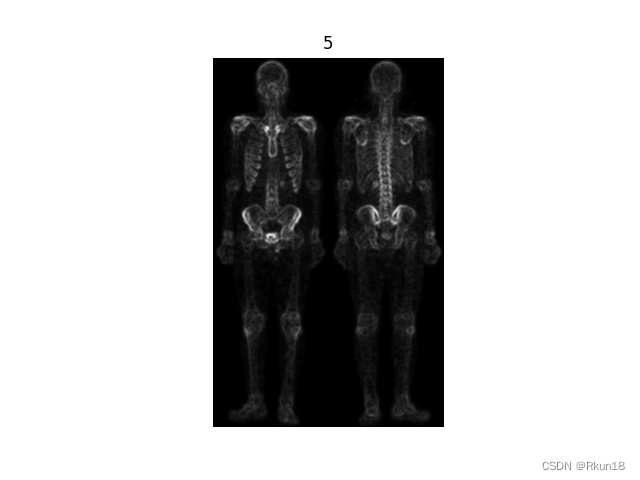

5:均值滤波对4进行平滑:

图4进行空间平滑滤波得到图5,保留图像边缘信息,同时减小了噪声。